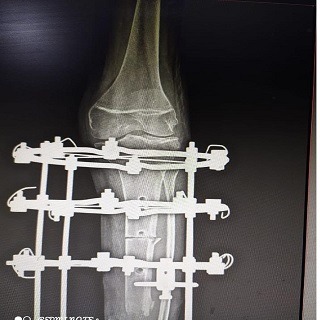

Malunion and Non-union of Bones: Using specialized techniques like Ilizarov and LRS (Limb Reconstruction System) for complicated long bone fractures.

Ilizarov Technique: A revolutionary method to treat bone defects, infections, and lengthening procedures.

LRS (Limb Reconstruction System): Used for treating non-unions and correcting bone deformities.